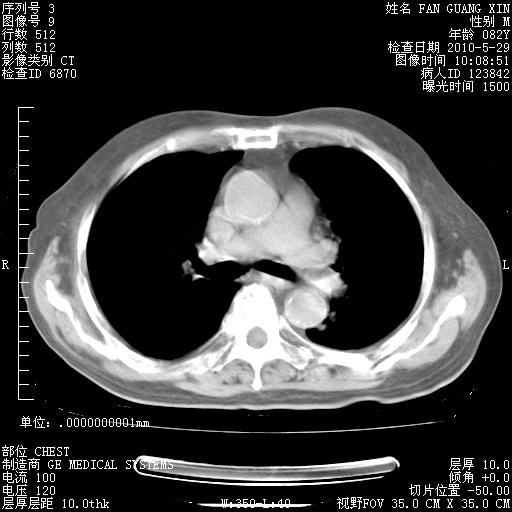

再治疗10天后的肺部CT 纵膈窗

阅读此次胸部CT,肺间质渗出性改变较入院时有吸收。目前从体温、白细胞、中性分叶明显增高,肯定存在细菌感染(发生医院感染哦,若无消化道及泌尿系统等感染的依据,肺部感染可能大)。若你院头孢哌酮舒巴坦钠耐药率较高,同意你的方案,若48小时体温仍高,可考虑使用碳青霉稀类抗菌药物,同时可予超声雾化、注意滴数时加大液体量。白蛋白33.30g/L较低哦,需加强营养等支持治疗。